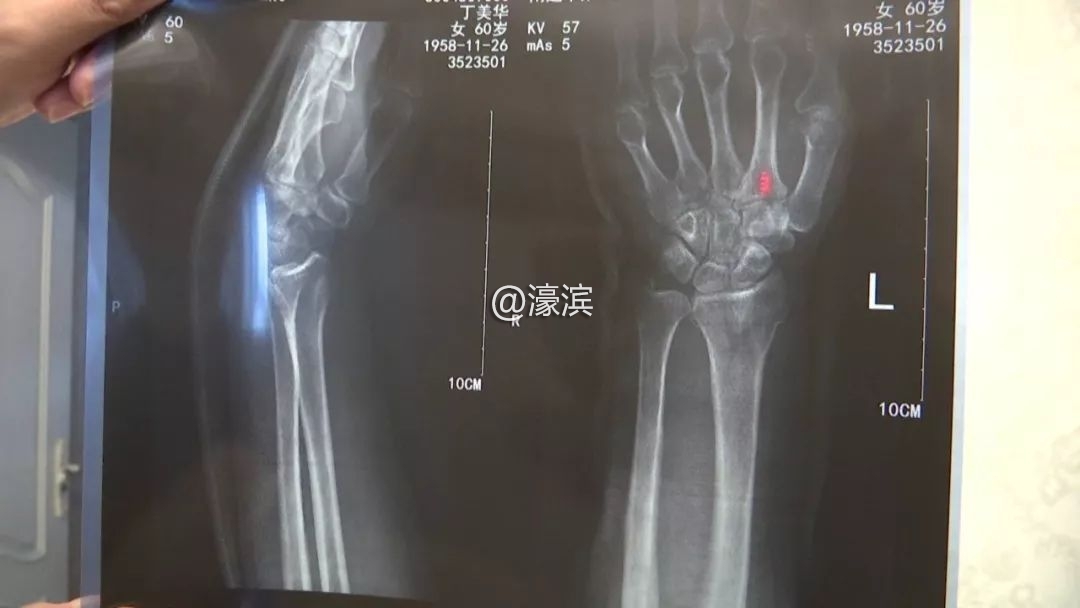

丁美华到医院做了CT,结果是左手腕骨折,正在接受治疗。